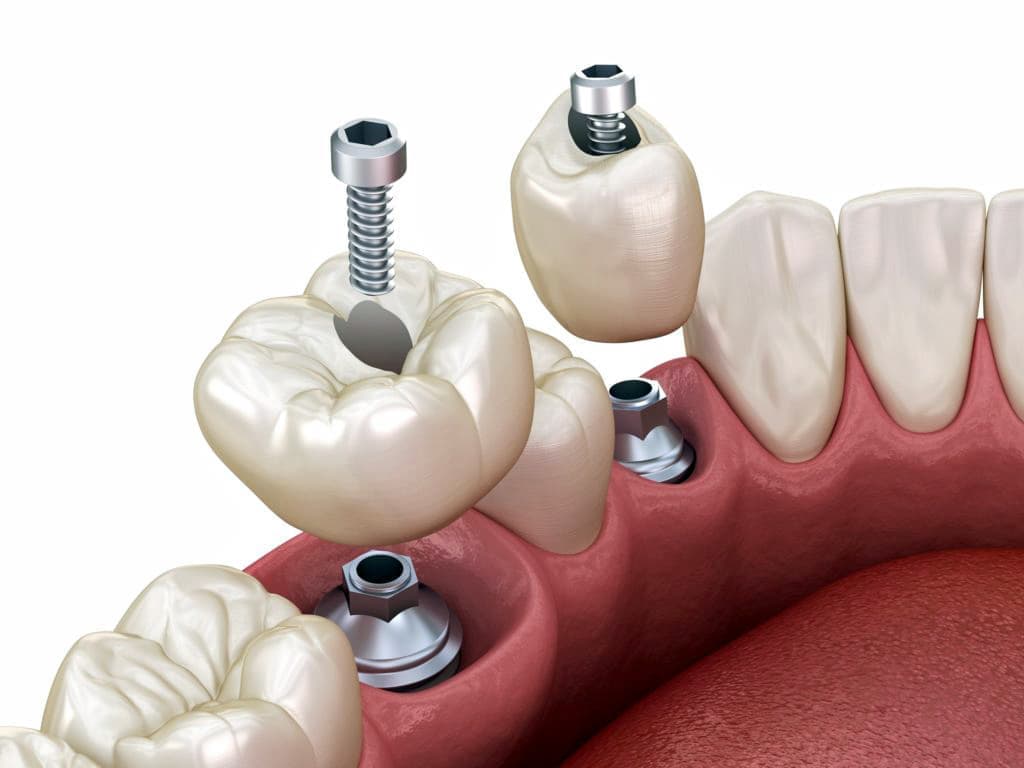

インプラントとは、顎の骨に人工歯根となる金属を埋め込み、それを土台にして、天然の歯と同じような人工の歯を取り付ける治療方法です。

埋め込む金属に生体との親和性が高いチタンが使われる事が多く、チタンは長年の臨床研究でインプラントの素材として最も安全であり、また顎の骨としっかり結合することが確認されています。

天然歯のような見栄えだけでなく、これまでの入れ歯やブリッジでは満足することが難しかった「食べる・話す」という機能も回復できます。

食べ物のカスが挟まったり、留め金が見えるといったこともないので、衛生面や見た目からも、天然歯自分の歯と同じようにきれいで美しい状態を保てます。